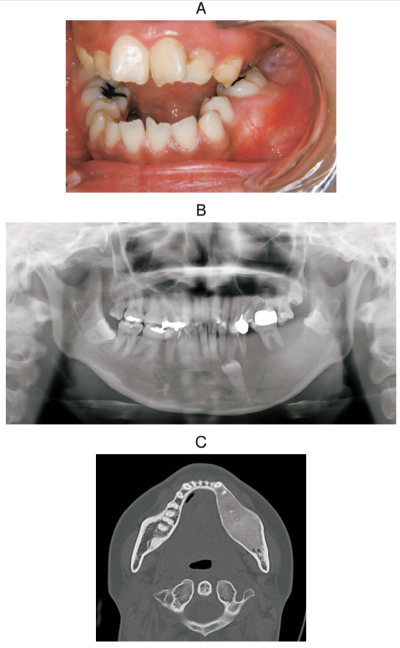

24 歳の女性。下顎左側臼歯部歯肉の膨隆を主訴として来院した。1年前に気付いたが、疼痛がないためそのままにしていたという。初診時の口腔内写真、エックス線画像 、CT及び生検時の H-E染色病理組織像を別に示す。